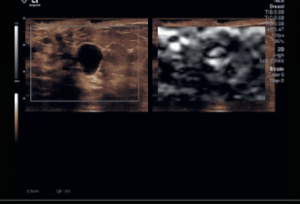

The Departments of Medical Physics and Radiology at the University of Wisconsin School of Medicine and Public Health provide a rich environment for performing research in Ultrasound Imaging (US). The infrastructure includes a wealth of equipment, support staff, and researchers with clinical and technical expertise. Please see below for a brief overview of the US equipment, personnel, and areas of ongoing research. You can also follow the links to see more information about the research program, or to apply for time on the US systems to conduct your own research project.

Housed within WIMR is a core group of investigators specializing in US research. This is a multi-disciplinary group, composed of faculty, post-docs, and students from the Departments of Medical Physics, Biomedical Engineering, Mechanical Engineering, Radiology, and others. The main emphasis of the research is developing new acquisition and analysis methods for enhancing the capabilities of clinical US imaging. Current projects focus on shear wave elastography, investigations of the underlying collagen microstructure of tissues, breast elastography, multi-scale/multi-modality imaging, platelet rich plasma injections and many other topics.

US research is performed by a number of investigators beyond the core group as well. Within the University of Wisconsin and throughout UW Health, there is a long-standing tradition of inter-departmental and inter-disciplinary collaborations that are necessary for advancing clinical and basic science. We work within multiple different project areas including Neurosurgery, OB, Orthopedics, Sports Medicine, Nephrology, the Laboratory for Optical and Computational Instrumentation, and many others.